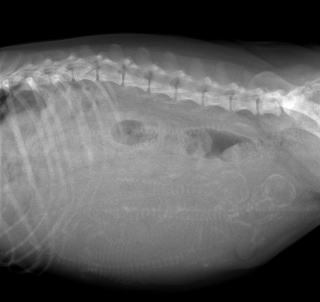

・P組長女Runa レントゲン撮影結果 2019.10.16更新

交配57日目 4頭居ます。

我が家で生まれたRuna(P組長女 父:CH John、

母:INT.CH Faith)ちゃんを、千葉県木更津市まで

お迎えに行って来ました。母子共に、元気に育ってい

て、大きなお腹になっていました。

早速、レントゲン撮影したところ、4頭の子犬達が

写っていました。

父犬は、CH Manchesterです。

出産予定日は、10月22日(火)になります。